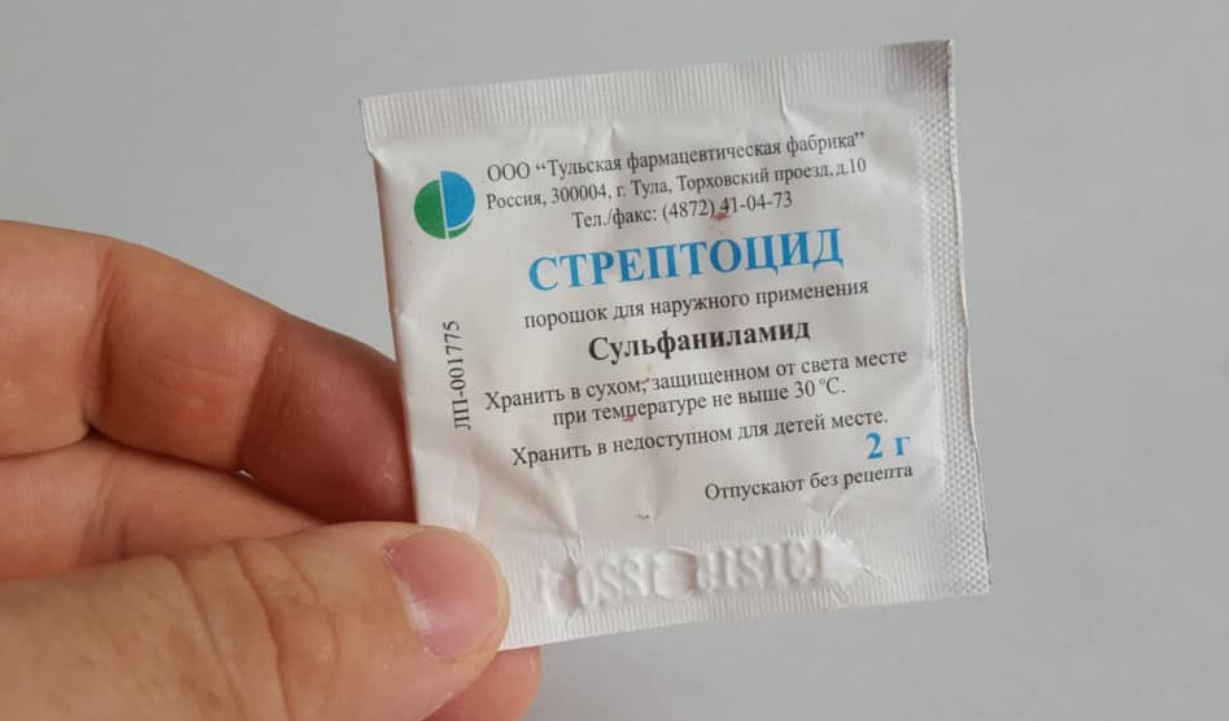

→ Есть мнение о том, что цветочная пыльца усиливает лечебный эффект многих лекарственных веществ.

В цветочной пыльце обнаружены стимуляторы роста и антибиотик, который задерживает развитие опухоли (в эксперименте).